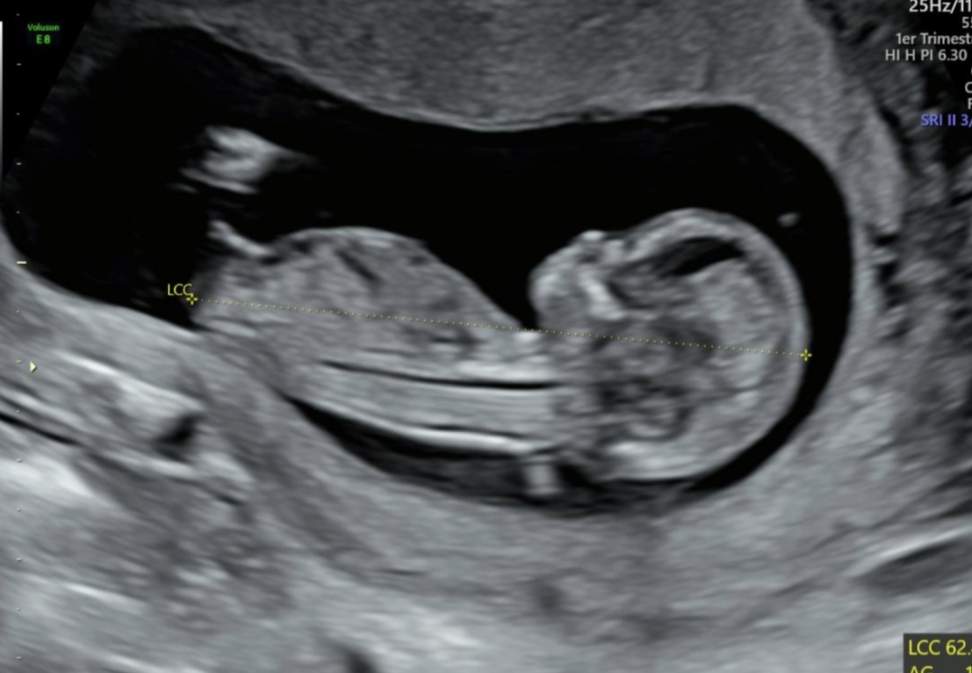

12주 각도법 투표 부탁드려요!

빌리ai는 딸이라는데 장꾸맘님은 아들에 한표를 주셨네요. 동기님들은 어떻게 보이시나용..ㅜㅜ?